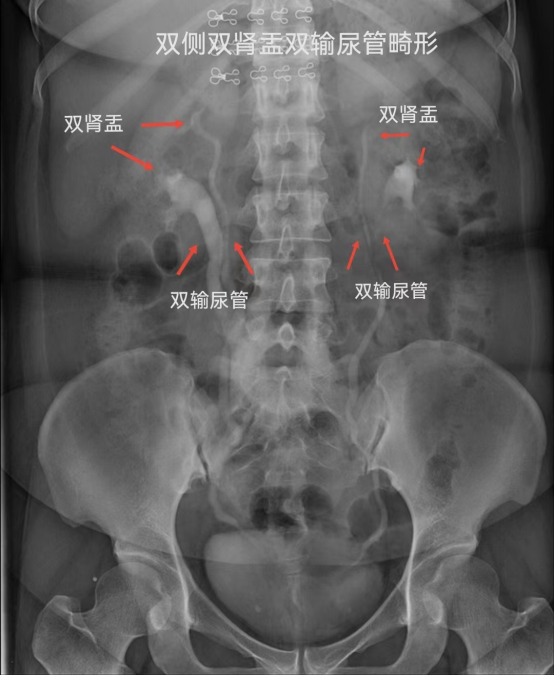

常规拍腹部仰卧位平片(KUB),准备好腹部压迫带,静脉注射造影剂,同时腹部加压,注射完后分别于7、15、30分钟摄片及解除压迫后摄片。

IMG_259IMG_260IMG_261IMG_262

静脉肾盂造影用于检查泌尿道器质性病变,可观察到尿路梗阻部位及原因。显示尿路结石造成的造影充盈缺损,对泌尿系病变有重要的诊断意义,静脉肾盂造影是放射科的常规检查项目,为进一步治疗提供可靠的指导意见及治疗方案。(供稿:放射科)